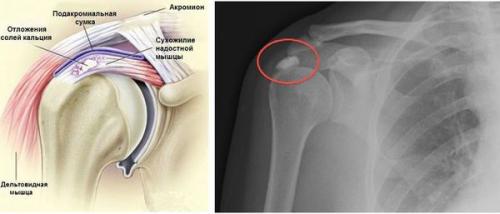

Рентгенография может выявить кальцификаты в сухожилиях или субакромиальной сумке. На ультразвуковом исследовании определяется утолщение сухожилий, наличие выпота в сухожильных влагалищах и субакромиальной и поддельтовидной сумках, кальцинаты с воспалительными участками вокруг них.

На рентгенограмме и ультразвуковом исследовании могут выявляться признаки остеопороза , остеосклероза, остеофиты (краевые разрастания костной ткани) в местах прикрепления сухожилий мышц, кальцинаты, утолщение и сморщивание капсулы плечевого сустава.